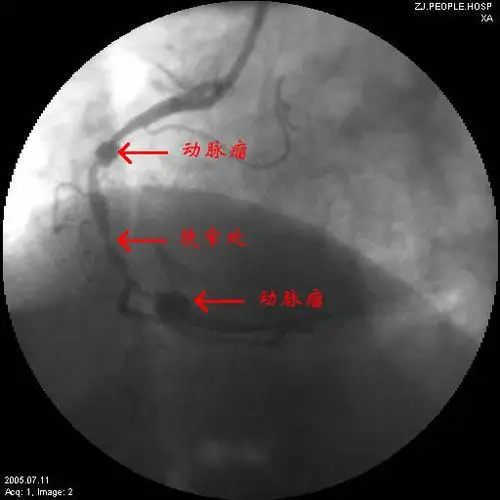

双侧冠状动脉瘤

我科使用冠脉带膜支架治疗冠状动脉瘤

冠状动脉瘤

先天性冠状动脉瘤